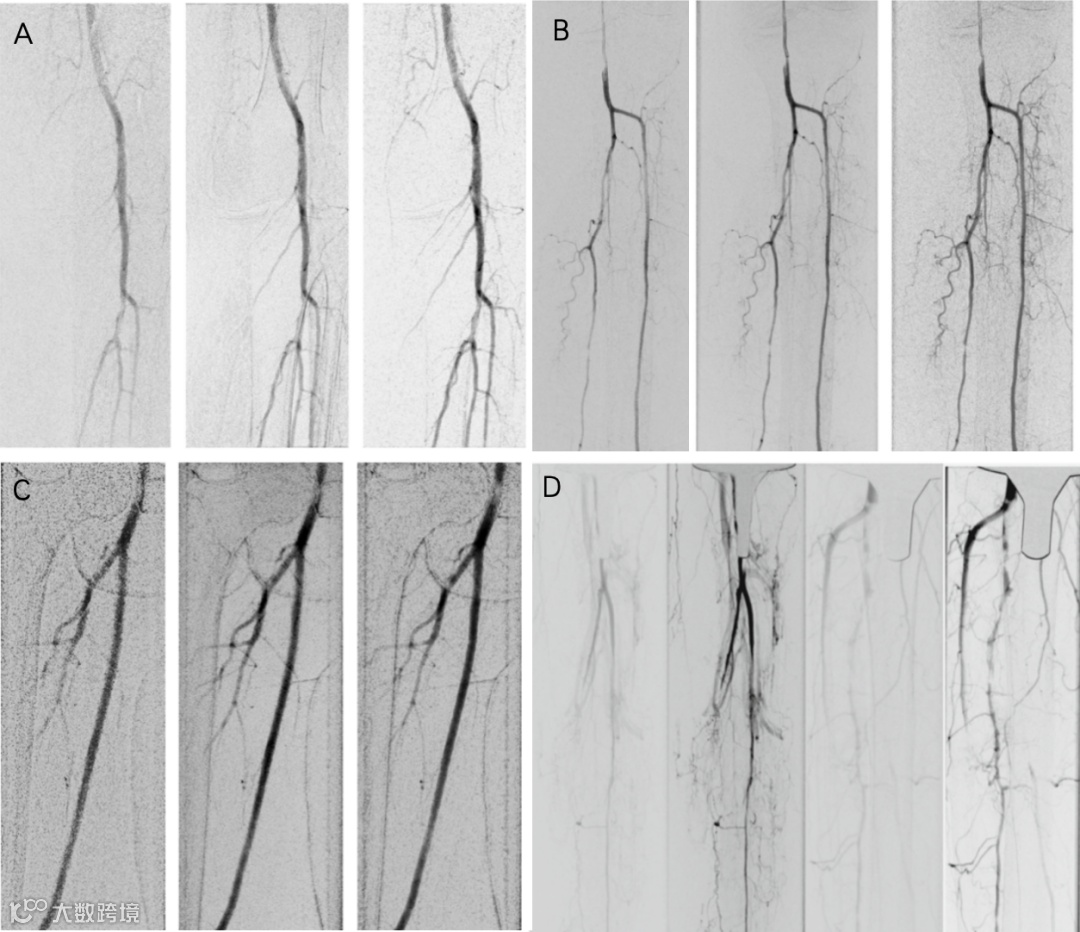

研究指出,DVA在下肢血管造影中的应用能够显著降低辐射暴露,抵消金属植入下肢血管造影图像质量的损害,同时提升图像清晰度,另外可显著减少辐射剂量(文献报道对照DSA可减少约70%),尤其在高龄患者或需要多次检查的情况下,具有重要的临床价值。

图1. DSA-DVA下肢动脉图像对照:A-C. DSA(左z)-DVA1(中)-DVA2(右)/ D. DSA(左)-DVA(右)在下肢金属植入物干扰下图像质量对照;